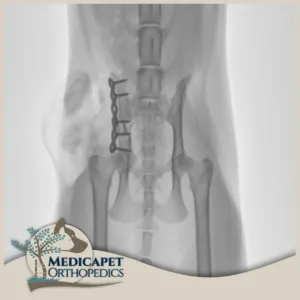

Plak Uygulamaları

Medicapet’de açık operasyon ve internal fiksasyon gerektiren kırıklarda yüksek kaliteli titanyum plaklar ve vidalar kullanıyoruz. Plak uygulamalarımızda kırık oluşan bölge eski konumuna getirildikten sonra kemiğe uygun plak tipi seçilerek bölgeye yerleştiriliyor, mümkin olan en az vidanın kullanılması ile kırığı onarıyor, gereken durumlarda iyileşmeden sonra implantı geri çıkarıyoruz. Plak uygulamalarımızdaki temel prensibimiz minimal invaziv yöntemleri kullanmaktır. Böylece mümkün olan en küçük boyuttaki kesiyi yaptığımız için iyileşme sürecini de hızlandırmış oluyoruz.